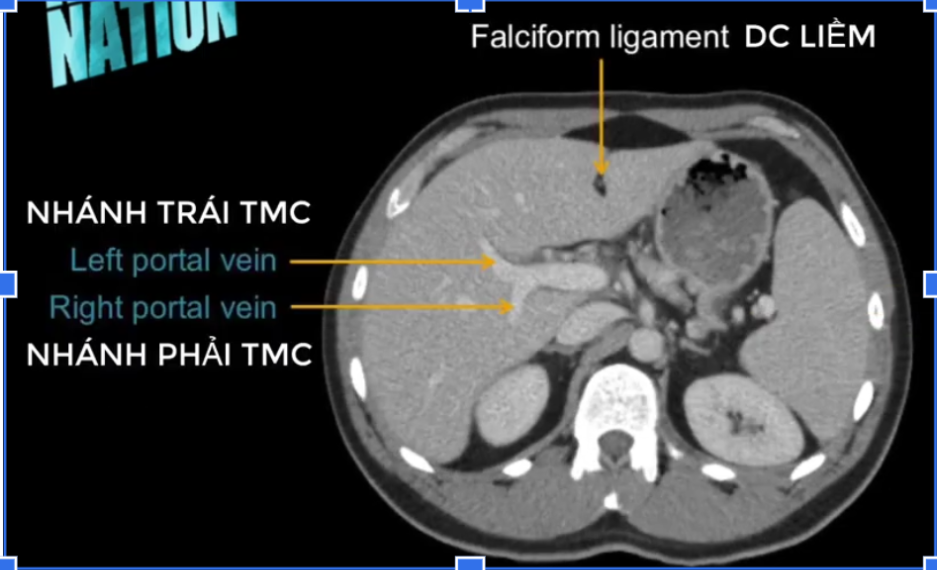

TM gan ở đâu? TM chủ dưới ? ĐM chủ?